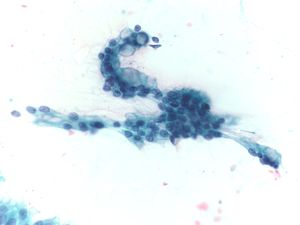

Solid Pseudopapillary Neoplasm [SPN labeled slides]

Key Cytological Features: Solid-Pseudopapillary Neoplasm

- Solid cellular smear pattern with or without branching and papillary cell clusters

- Fibrovascular myxoid stromal papillae are characteristic Cells are relatively bland with little anisonucleosis and no mitotic activity

- Nuclei are round to oval with frequent nuclear grooves or focal indentations and finely granular chromatin and inconspicuous nucleoli

- Cytoplasm is typically scant and ill-defined but can be moderate with small perinuclear vacuoles or intracytoplasmic hyaline globules, best detected on air-dried smears

- Smear background may be clean or filled with hemorrhagic cyst debris, foamy histiocytes and multinucleated giant cells